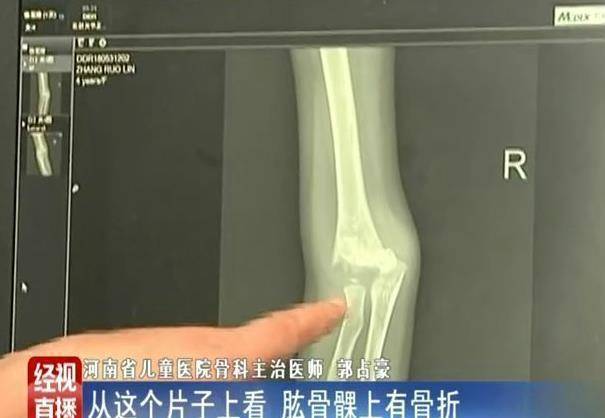

均衡车的速率常快的,之前就有一个5岁的孩子,正在小区里游玩着均衡车,但由于得到均衡,孩子就俄然摔倒正在地。只是,孩子没能站起来,随后家幼迎孩子去病院,查抄得知,孩子骨折了。

为孩子诊治的大夫说,不中才一个月摆布的时间,就曾经有十多个孩子由于主电动均衡车上摔下来,去他这里诊治的。这些孩子,小的3岁,大的也才十多岁。